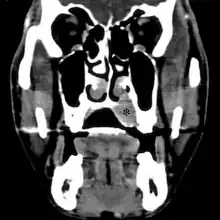

![]() ![]() | |

| Top: Ewing sarcoma of the thigh bone on a child's CT scan Bottom: Extraskeletal Ewing sarcoma of the hard palate | |